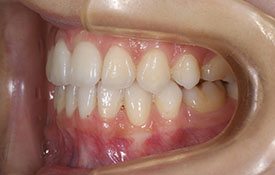

インビザラインの治療例:CASE-2

| プロフィール | 15歳 男性 |

| 所見 | アメリカから転院されて来られた方です。 インビザラインで上下顎の矯正治療を開始し下顎はアメリカで終了しており、上顎のみ治療の後期を担当しました。 アイライナーの装着は、1日平均22時間ほどでした。 |